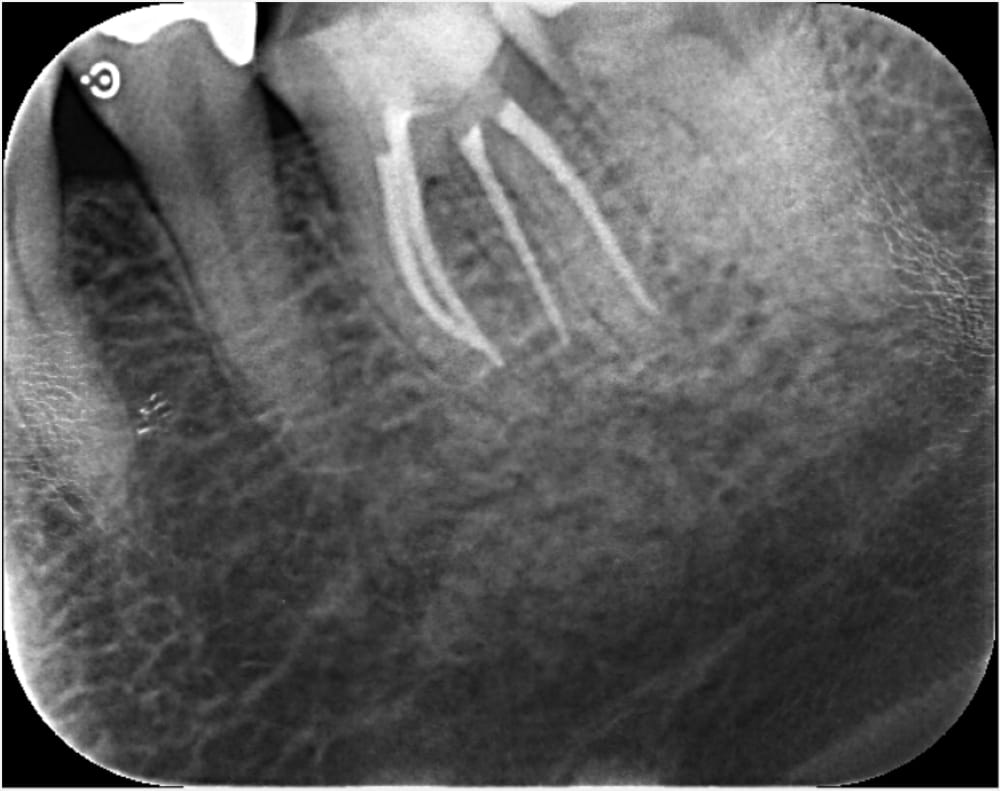

精密根管治療 2回目

2回目の来院時には、当初抱えていた強い痛みはかなり軽減していました。

根管内を徹底的に清掃し、充填のためのガッタパーチャポイントを試適し、根管充填+コア築造まで完了しました。